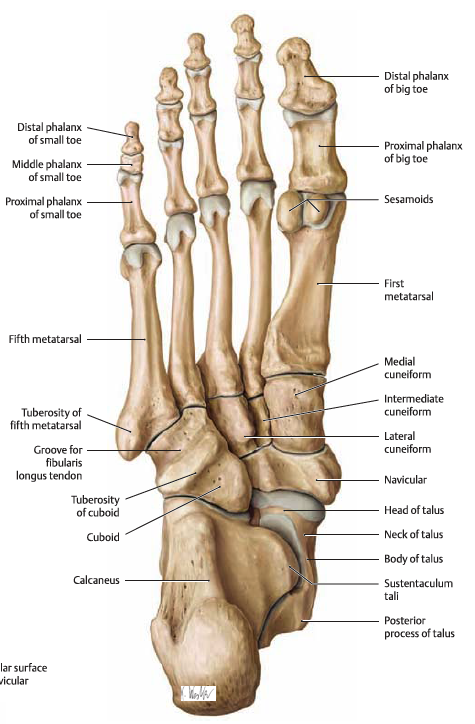

경골 - 거골 - 종골 - 주상골과 입방골, 설상골 - 중족골

- 까치발로 서면 경골 - 거골 - 주상골 - cuneiform bone - metatsal bone